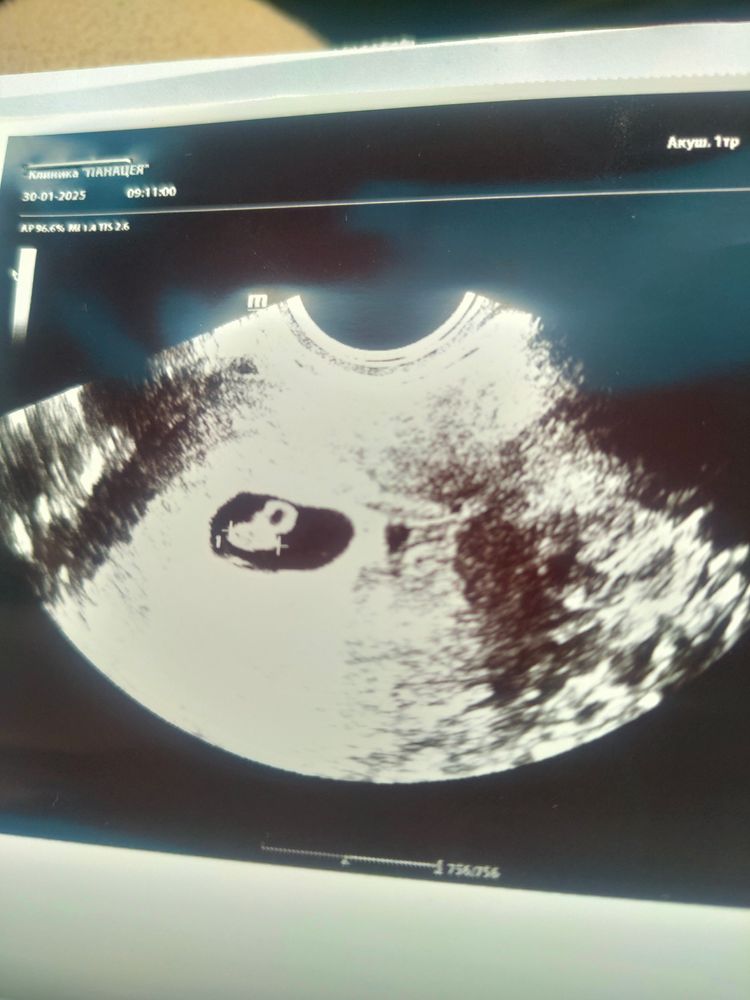

Наше знакомство в 6 недель

Вот мы увидились наконец-то! Такая маленькая кнопочкая, но уже такая хорошенькая, родная и долгожданная. КТР 6,7 СВД 18. Сердцебиение + ♥️